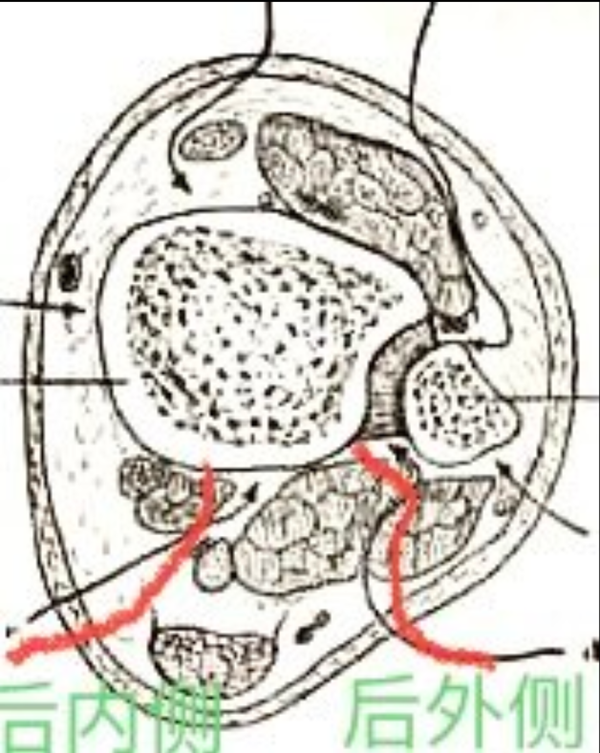

图2 胫骨远端解剖分区,红色内侧柱;蓝色外侧柱;绿色后侧柱

图6 显露后柱骨折的后外侧与后内侧切口